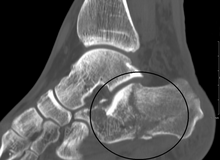

Conventional radiography is usually the initial assessment tool when a calcaneal fracture is suspected. Recommended x-ray views are (a) axial, (b) anteroposterior, (c) oblique and (d) views with dorsiflexion and internal rotation of the foot. However, conventional radiography is limited for visualization of calcaneal anatomy, especially at the subtalar joint. A CT scan is currently the imaging study of choice for evaluating calcaneal injury and has substituted conventional radiography in the classification of calcaneal fractures.[12] Axial and coronal views are obtained for proper visualization of the calcaneus, subtalar, calcaneocuboid and talonavicular joints.

Calcaneal fractures are categorized as intra-articular or extra-articular on the basis of subtalar joint involvement. Intra-articular fractures are more common and involve the posterior talar articular facet of the calcaneus. The Sanders classification groups these fractures into four types based on the location of the fracture at the posterior articular surface. Extra-articular fractures are less common and may be located anywhere outside the subtalar joint.[12] Extra-articular fractures are categorized depending on whether the involvement of the calcaneus is anterior (Type A), middle (Type B) or posterior (Type C).[14]